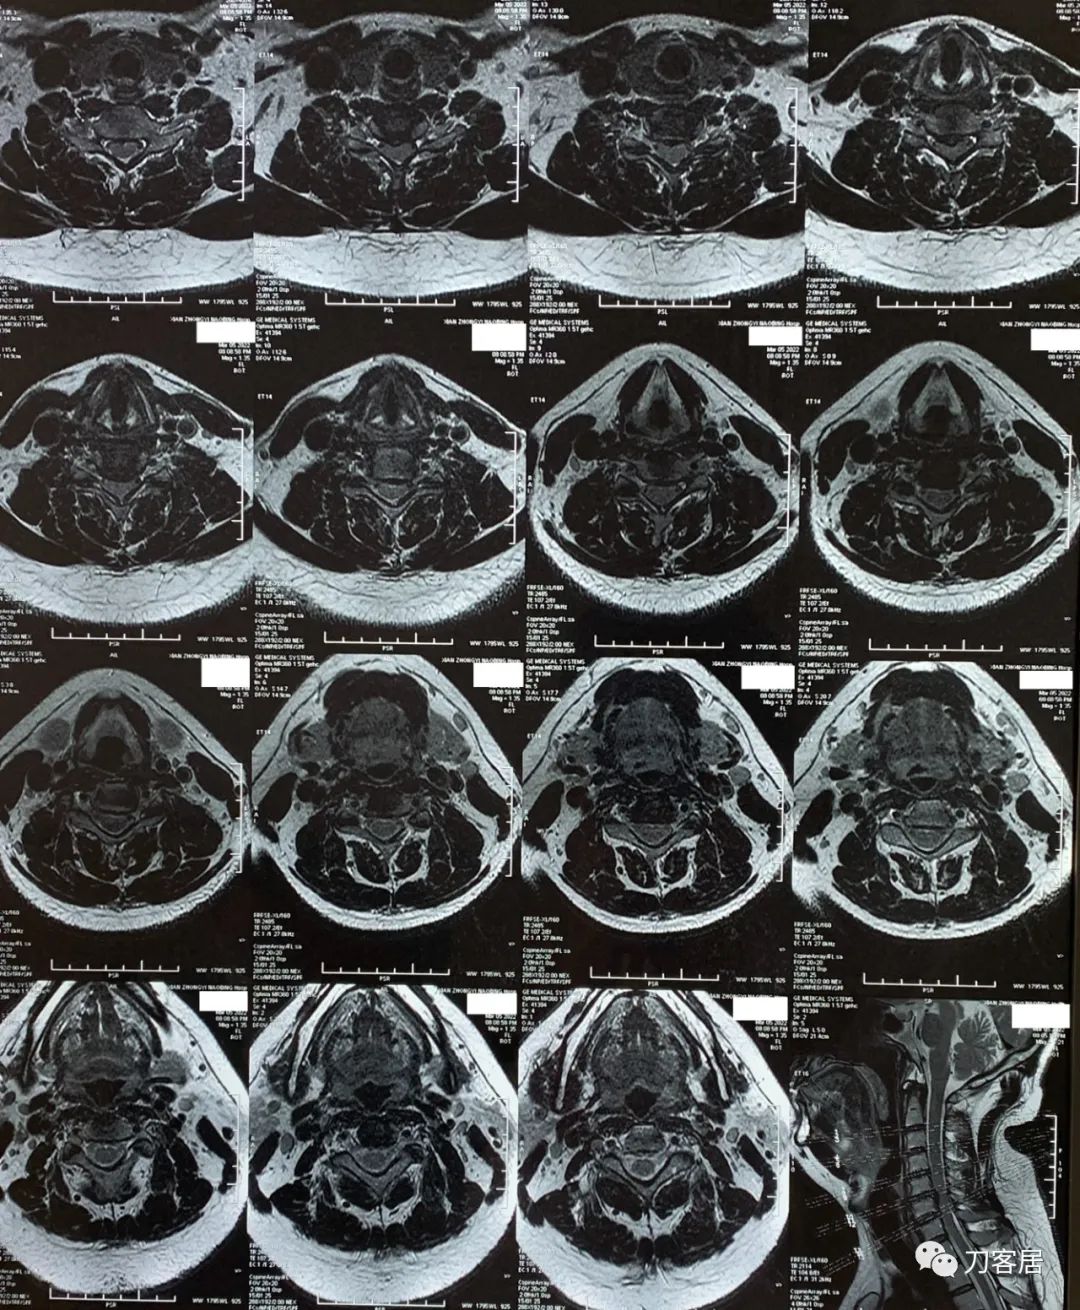

图1. 20220305颈椎MRI提示颈5-6椎间盘突出,椎管狭窄,脊髓受压。

图2. 20220305颈椎MRI提示颈5-6椎间盘突出,椎管狭窄,脊髓受压。

图3. 20220305颈椎MRI横截面,提示颈5-6椎间盘突出。

自带颈椎MRI提示颈5-6椎间盘突出,不严重。